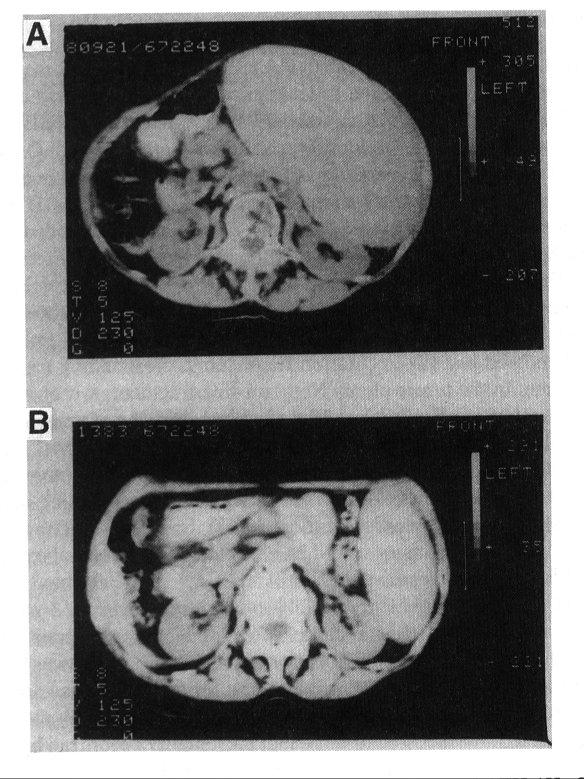

The first patient to be treated with CAMPATH-1H was a lady suffering from non-Hodgkins lymphoma in leukaemic phase [25]. She had a very high white cell count, bone marrow completely packed with tumour cells and gross splenomegaly. Six months previously, she had been treated with CAMPATH-1G which gave a partial response but had been discontinued because of an allergic type of reaction. Only a small amount of CAMPATH-1H was available and it was administed in small doses (1-20 mg) over a period of 30 days (total 120 mg). Even to an untrained observer the response seems quite remarkable (Fig 1).

Figure 1. Treatment of non-Hodgkin‘s lymphoma with CAMPATH-1H.

Computed tomographic scans showing the extent of splenomegaly before (A) and after (B) treatment. (Reproduced with permission from ref 25.)

The spleen size was reduced from 4.5 kg to 0.6 kg. Tumour cells could no longer be found in the blood or bone marrow and they began to be replaced by normal blood elements. Analysis of DNA from a bone marrow aspirate before treatment showed just two restriction fragments corresponding to biallelic Ig rearrangement in the tumour clone. No germ-line fragments were visible at all. In marked contrast, a sample taken 28 days after the beginning of treatment showed only germ line genes and no sign of the Ig gene from the tumour (Fig 2).